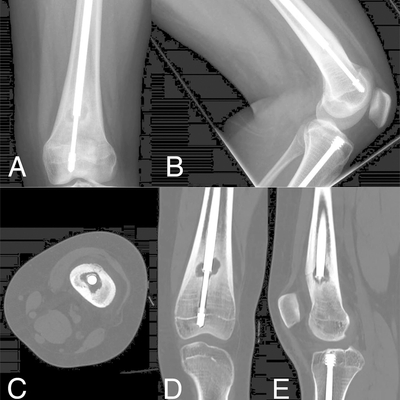

Click on an image below to view more info.